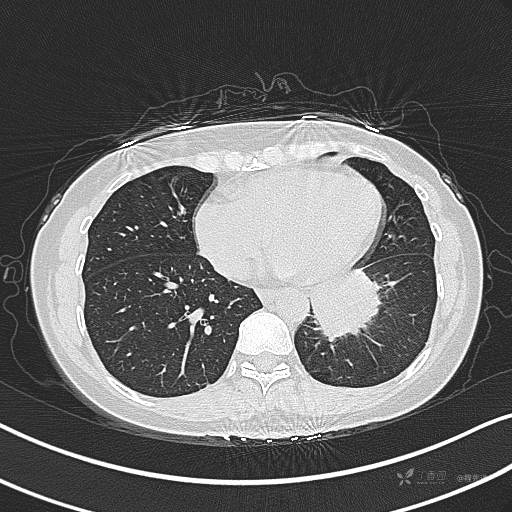

CT平扫

肺窗

CT值:平扫:31HU,动脉期:74HU,静脉期:84HU